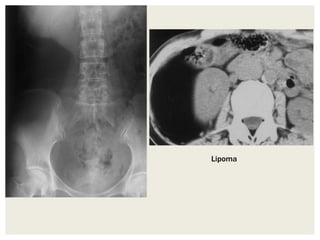

Lipomas

CT

• Homogeneous low attenuation mass (typically approximately -

65 to -120 HU).

• Thin fibrous septa may traverse the lesion. Lipomas having

prominent fibrous septa and nodularity may mimic well

differentiated liposarcomas at imaging.

• When the mass is somewhat irregular and ill-defined, but

contains fat, the diagnosis of liposarcoma should be

considered.

• Findings that suggest that a fatty mass is more likely to

malignant than benign include:

• Soft tissue septa >2mm thick

• Septal irregularity or bulging

• Obvious enhancement

Lipoma